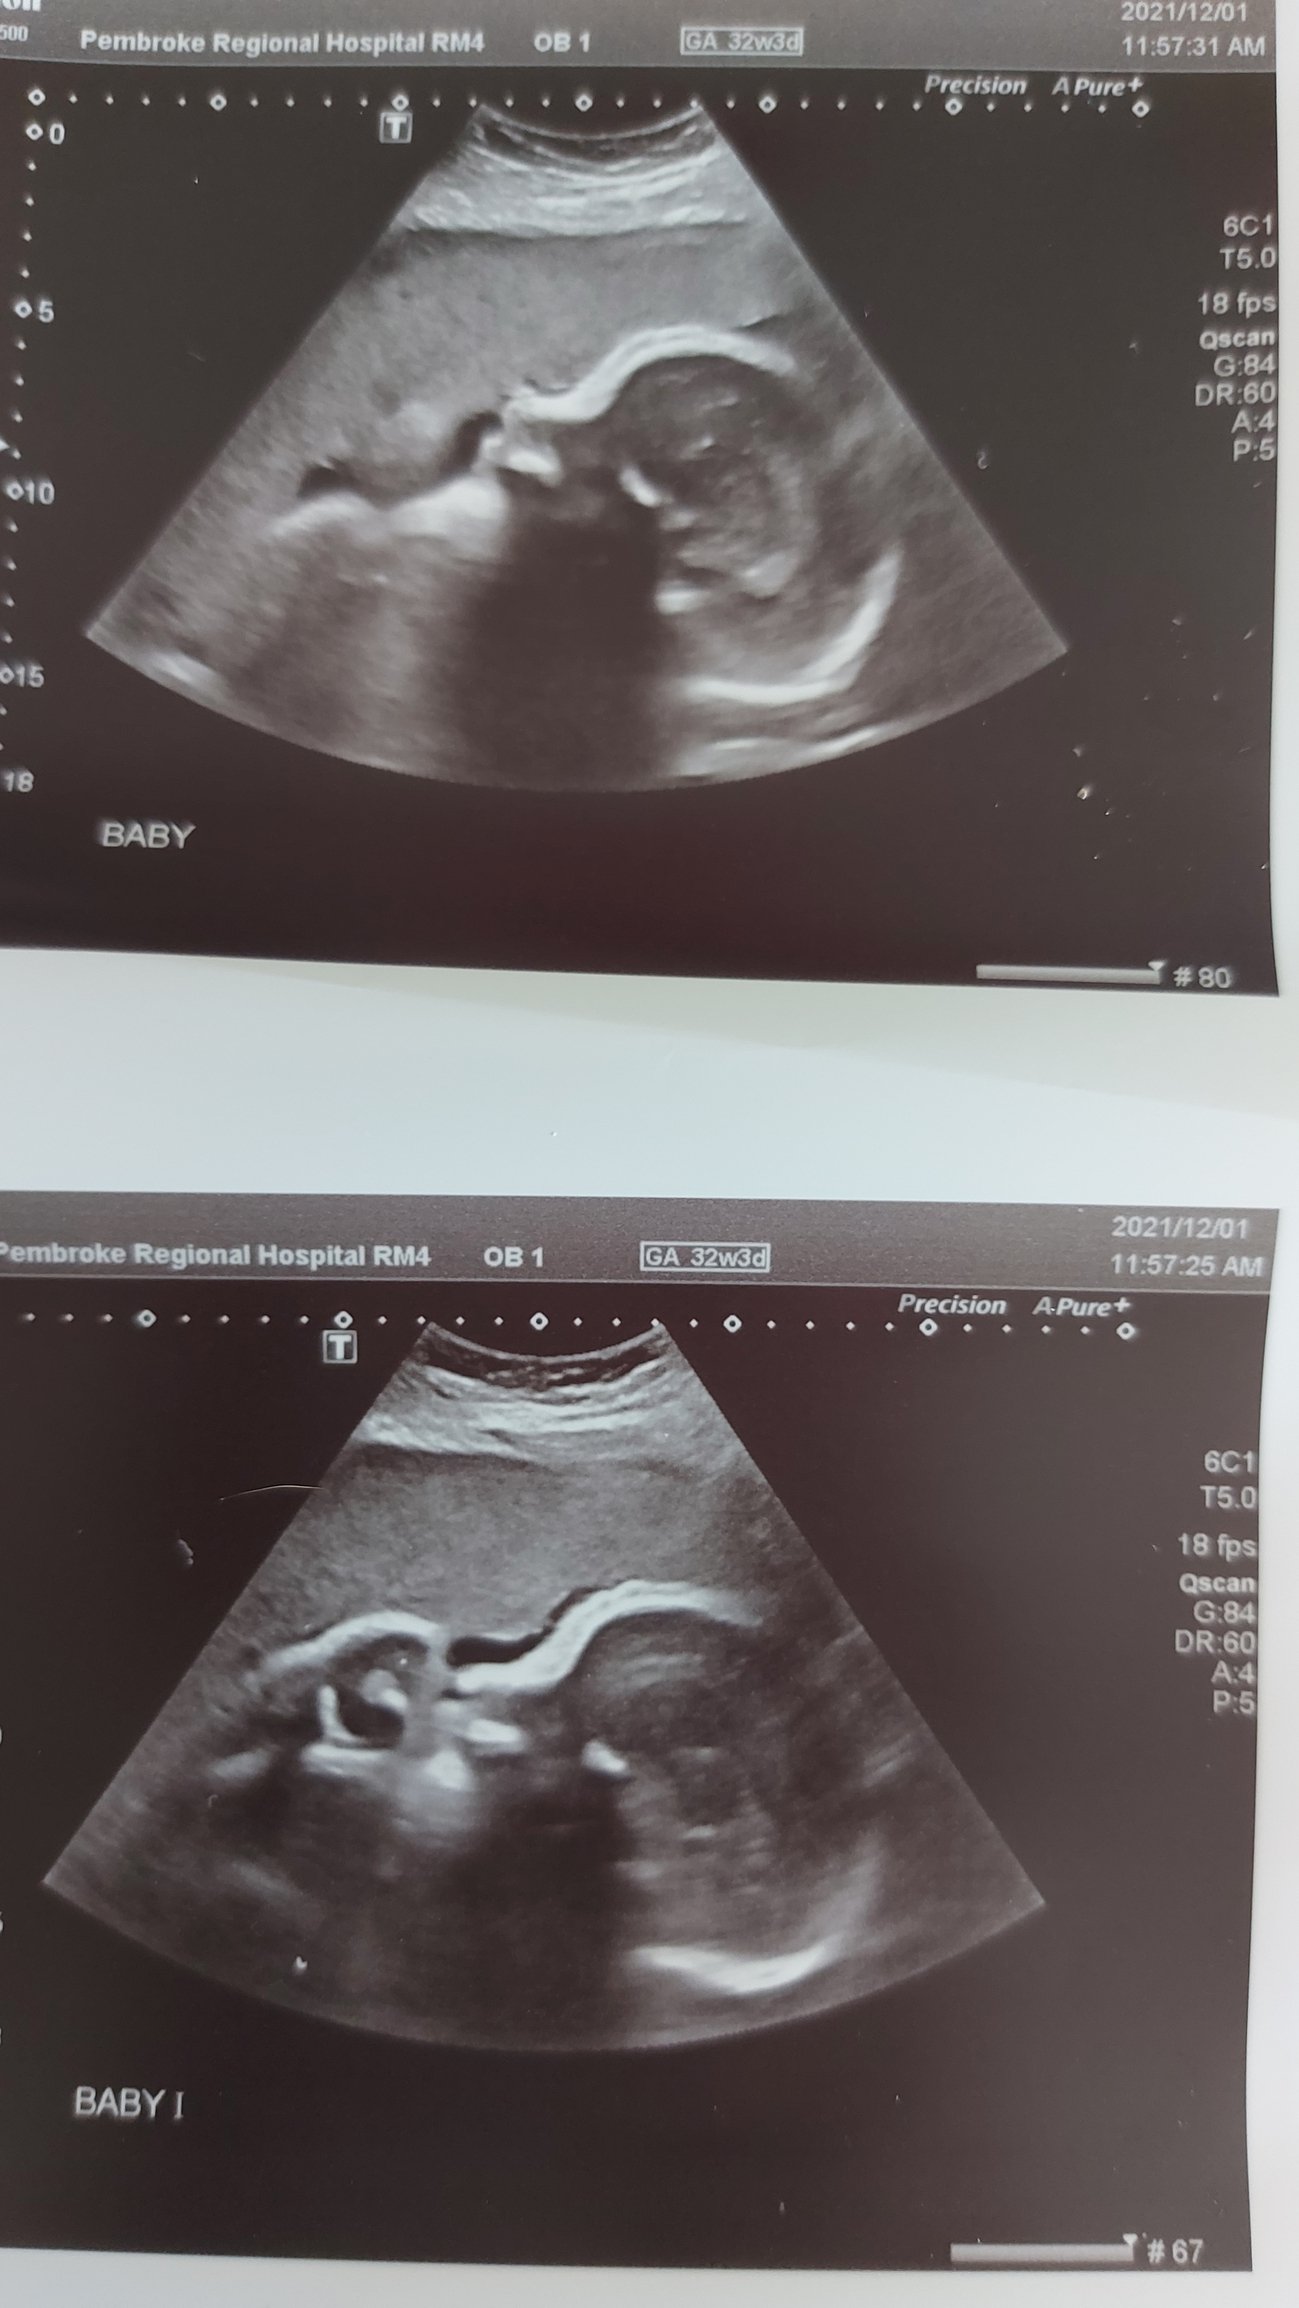

@Limes030 I was scheduled for one at 32 weeks but had to move it up to 29 weeks due to measuring big. Getting another one at 33 weeks to see how we're looking.